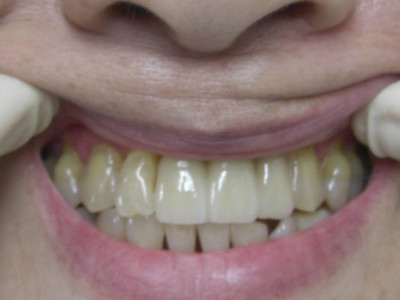

午前中のオペ後に前歯部に最終の上部構造体をセットさせて頂いた患者様がいらっしゃいましたので、ご了解の上で画像をアップさせて頂きました。

e-maxにて作製させて頂きましたが色調も合い患者様にも大変満足して喜んで頂きました。